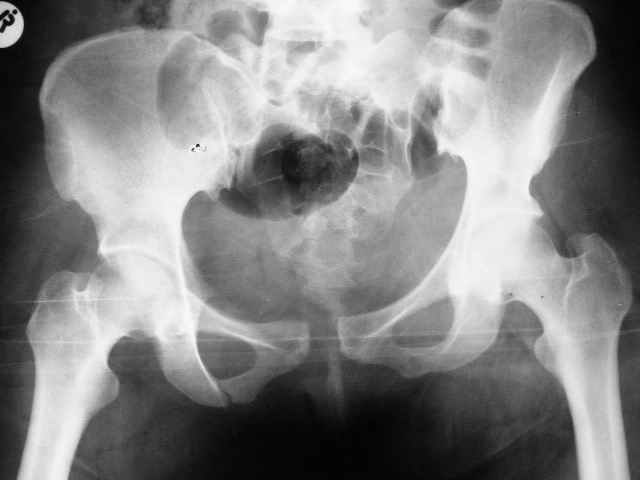

Больная 28 лет от роду попала в ДТП 12.12.04Что бы вы предложили.заранее признателен,Евгений И Чекашкин

Сегодня утром прооперировал: на симфиз пластину на 4 винтах и два 6.5 мм винта с неполной резьбой на левое крестцово подвздошное сочленение. (пришлось открыть - девушка весьма внушительной комплекции и пропальпировать крыло и ости не представлялось возможным, спасительного в таких случаях набора канюлированных винтов в госпитале нет). Проконтролировал качество репозиции ЭОПом - остался доволен.

В представленном ранее случае вертикальное смещение левой половины таза было минимальным и после плэйтин лонного сочленения незначительное вертикальное и заднее смещение полутаза было устранено, поэтому задняя фиксация и не составила проблемы. Но это свежий случай, оперированный через неделю, отсроченная фиксация, видимо, не будет столь простой. У меня спонтанно сложился подход к стабилизации переломов таза с нарушением тазового кольца: сначала передний отдел (пластина), потом задний - 2 винта. Имея ввиду свежие случаи, у вас такая же последовательность или наоборот. Про фиксацию реконструктивной пластиной на 10-12 винтах в данном случае даже и не подумал (обещали привести тазовый набор, но как- то не очень уверенно- праздники и у основной массы рождественское настроение), к тому же слишком обширная диссекция тканей, когда можно было обойтись меньшей кровью, да и передняя колонна вроде бы не задействована... Помимо ранней активизации и эластического бинтования ног или чулков как вы проводите профилактику тромбоэмболий, как рано после травмы назначаете антикоагулянты.